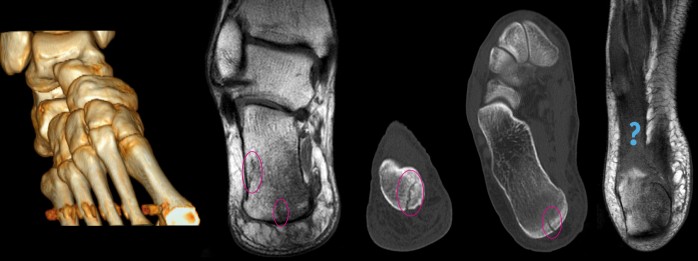

Häromdagen kom MR och CT bilderna som jag beställt från Medicinsk Röntgen. Först kunde jag inte öppna dem eftersom visningsprogrammet inte fungerade på Mac, sen när jag väl bytt dator visade det sig vara runt 200 skikt i varje bild… Efter endel analyserande och klickande fick jag fram ovanstående bilder.

Den första bilden visar min fot med CT. Häftigt!! Synd bara att inte hälen kom med… De två följande bilderna är rakt bakifrån och de två därefter är underifrån.